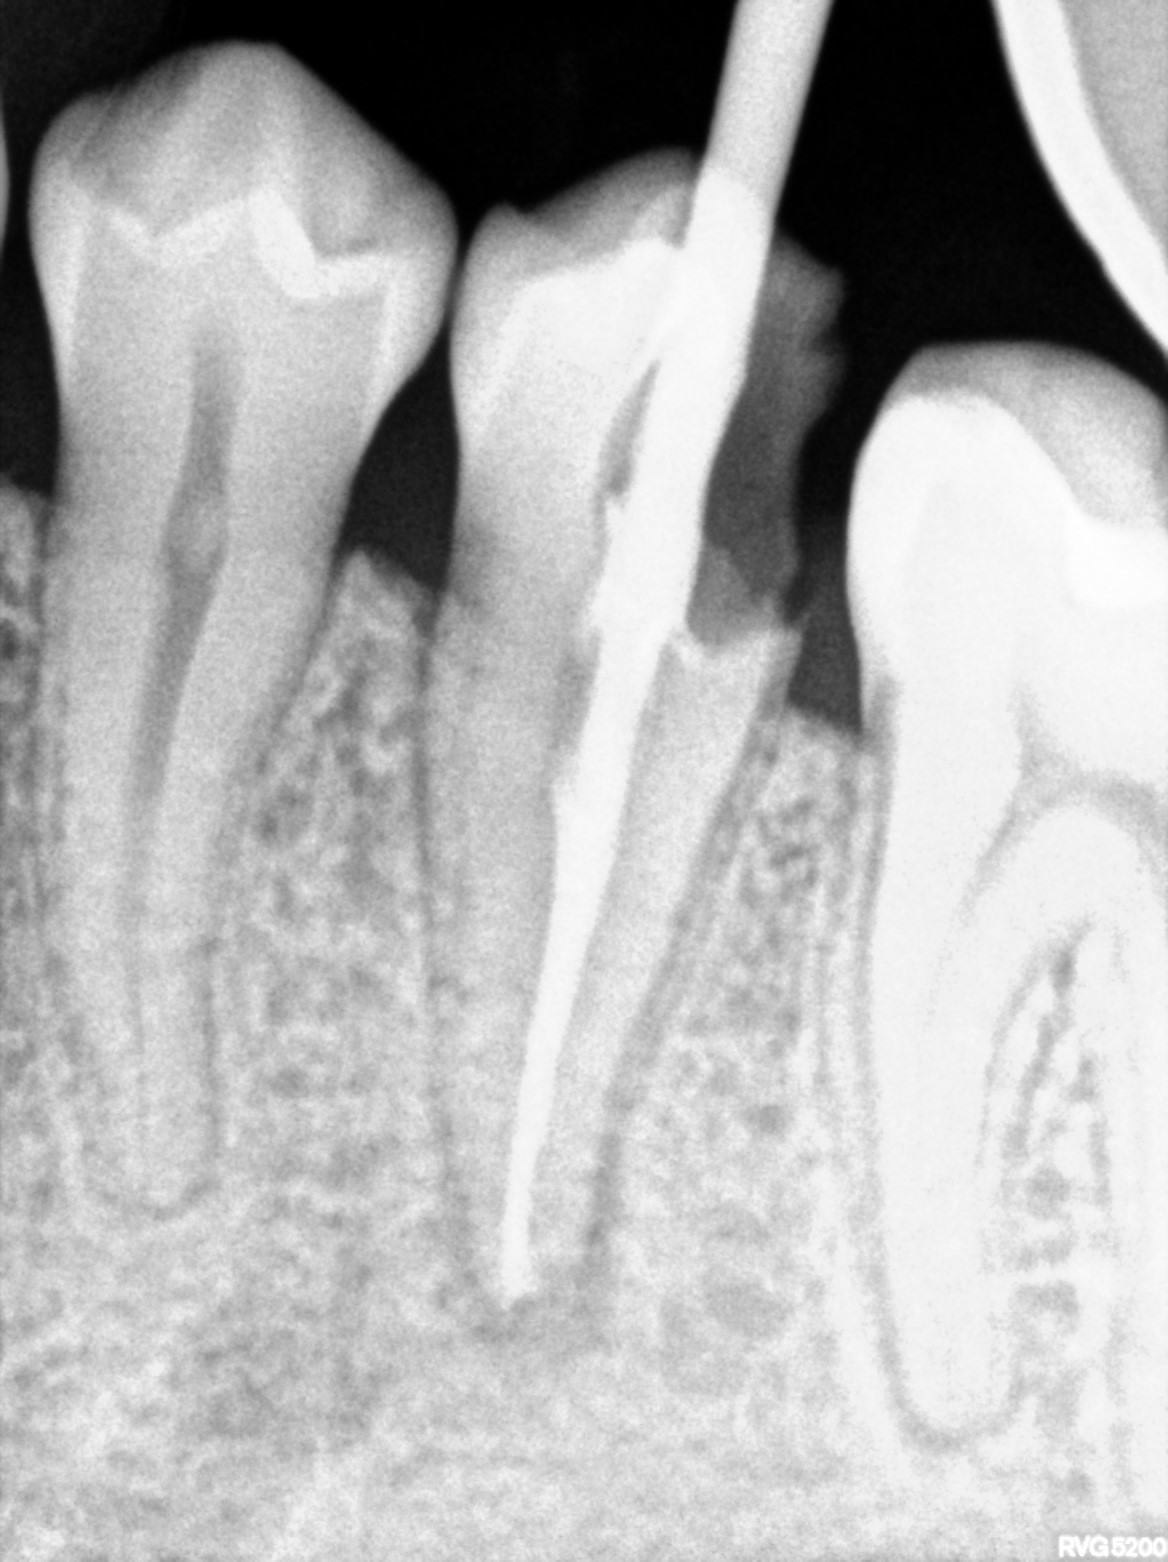

Dental Radiographs FHIR: DocumentReference · LOINC 24641-7

R55.jpg

24641-7

R59.jpg

R63.jpg